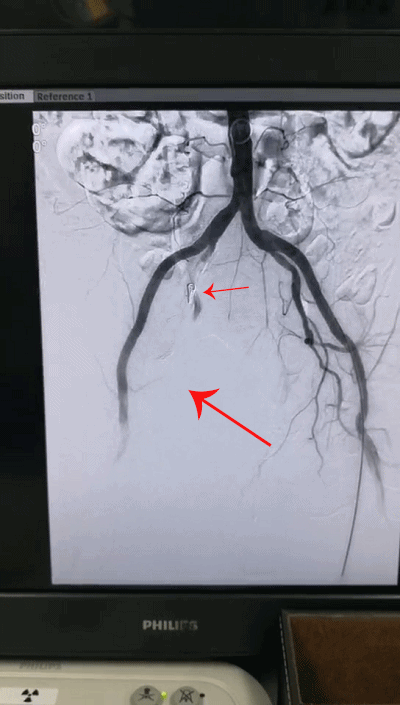

也正是在此时,短短数分钟之内,老人的血压迅速下降,心率不断加快,近乎休克,如不尽快处理,随时可能丧命,情况十分危急。深圳市中医院介入科紧急为老人实施了腹主动脉、髂动脉造影,迅速确定了出血位置,进行右侧髂内动脉超选择性栓塞治疗:通过微创介入技术[c1] ,使用微导管从大腿处进入动脉血管,在达到破损处后精准填入明胶海绵[c2] 与弹簧圈,栓塞封闭破损血管而成功阻止出血!手术之后,老人的血压和心率逐渐恢复正常,生命体征基本平稳。

栓塞后成功阻止出血